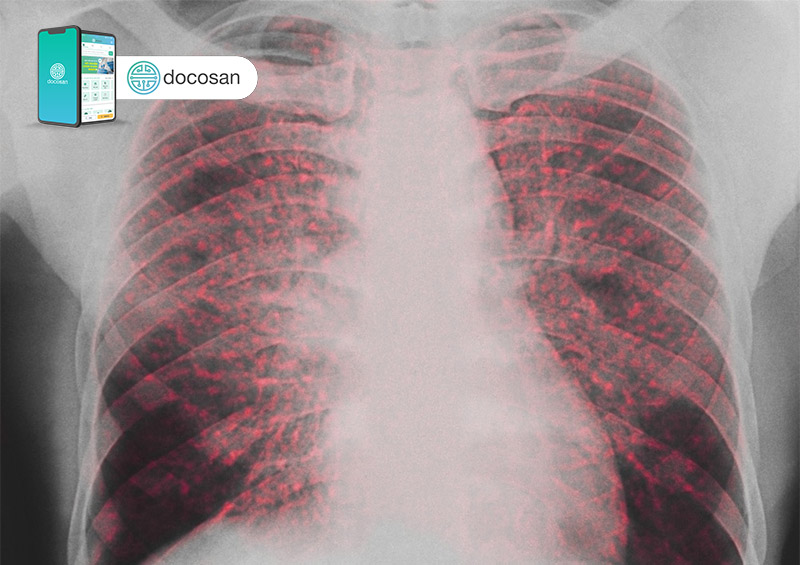

Một số người không có bất kỳ triệu chứng nào và tình trạng bệnh chỉ được phát hiện khi người bệnh thực hiện chẩn đoán bởi phương pháp chụp X-quang nhằm tìm kiếm các bệnh lý khác.

- Chụp X- quang

- Chụp CT